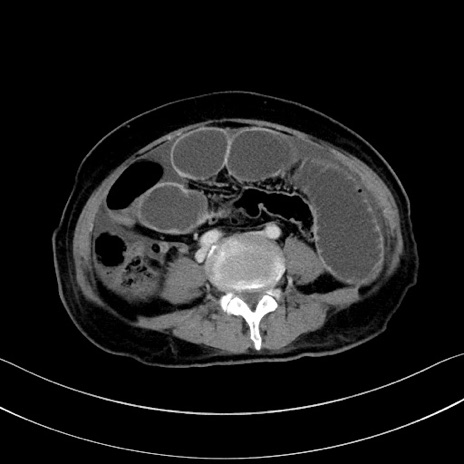

症例28(横断像)

【症例】60歳代男性

【主訴】嘔吐

【現病歴】胃癌にて胃全摘後。食思不振が悪化し、夜中に嘔吐することがある。

【既往歴】胃癌、胃全摘、脾摘、胆摘後

【データ】WBC 5900、CRP 10.56